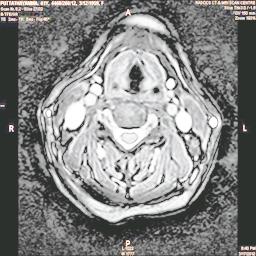

The developed algorithm presented in the previous section was coded using Matlab Version 8.0. The experiment was conducted by considering poor quality spinal cord images of having various lesions. The first column of Fig. 4 shows the axial view of neck spinal cord images of size pixels, respectively. The second column of Fig. 4 presents the same images enhanced using histogram equalization. As is evident from the results presented, the histogram equalization method performs global image enhancement operation which improves the contrast of an image but at the cost loss in image details. The third column of Fig. 4 shows the MSR based spinal cord image enhancement. It can be seen that from the result presented, MSR scheme improves the details that are not clearly visible in histogram equalization technique. In general, image enhancement achieved by MSR method is better compared to histogram equalization. However, the MSR method voilates gray world assumption. Therefore, the image enhanced by this scheme appears to be grayish. Although, numerous work have been reported for solving the problem due to gray world voilation, no work seems to developed for complete elimination.

The fourth column of Fig. 4 shows the image enhanced using Chao et al. []. It can be seen from the results presented that the reconstructed images of Chao’s method have black spots. The appearance of these dark patches degrades the visual quality of the enhanced image. The image enhanced using proposed multirate multiscale retinex image enhancement method presented in the fifth column of Fig. 4, overcomes the drawback of the Chao’s method. As we can see from the simulation results, image enhancement achieved by the proposed method has improved details with significant contrast enhancement. The enhanced images from the proposed method provides information to physicians, radiologists and researchers for various types of pathology detection.